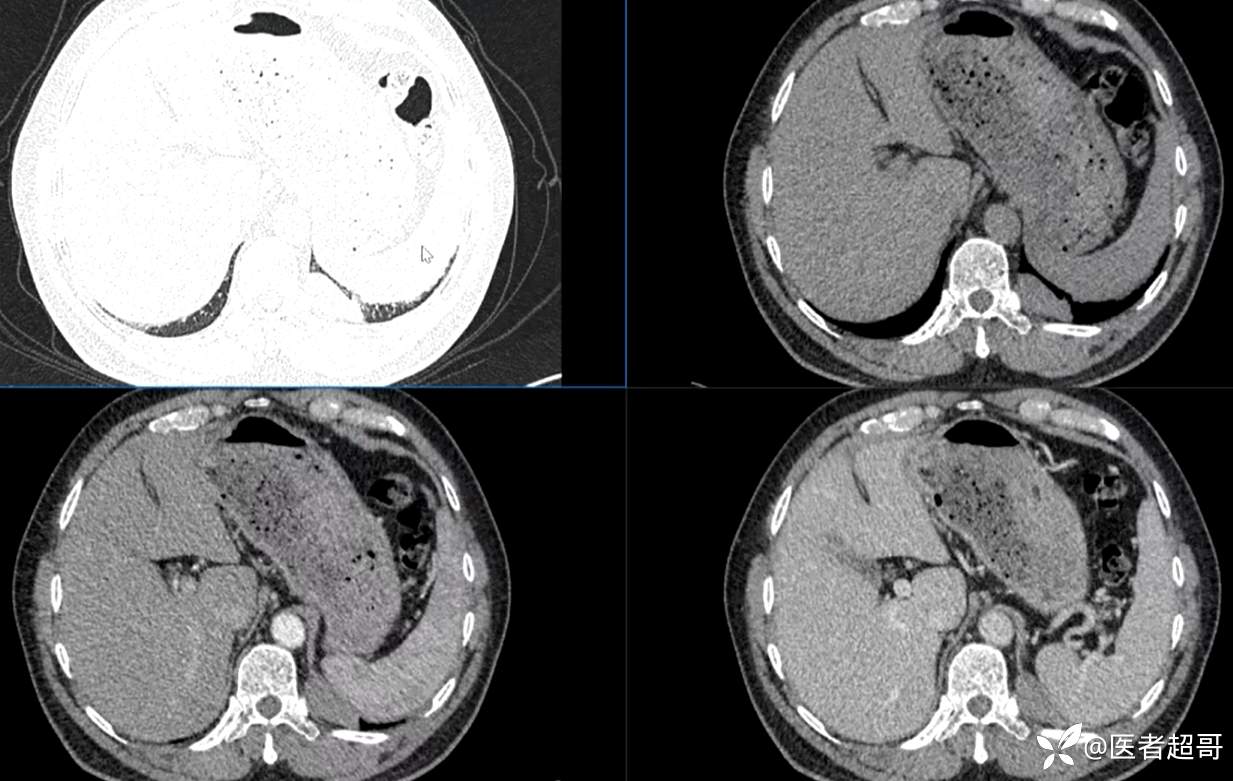

现病史:患者5月前因咳嗽、咳痰于当地医院就诊,完善胸部CT提示:胸膜多发占位,期间患者无胸闷、气紧、咳嗽、咳痰、心慌等不适,患者于我院门诊行胸部CT提示:左下胸膜增厚并见多个软组织密度结节影局限性凸起,较大者大小约3.5x2.2cm,增强扫描呈持续性轻度强化,考虑肿瘤性病变可能性大;门诊遂以:胸膜肿瘤收入我科。